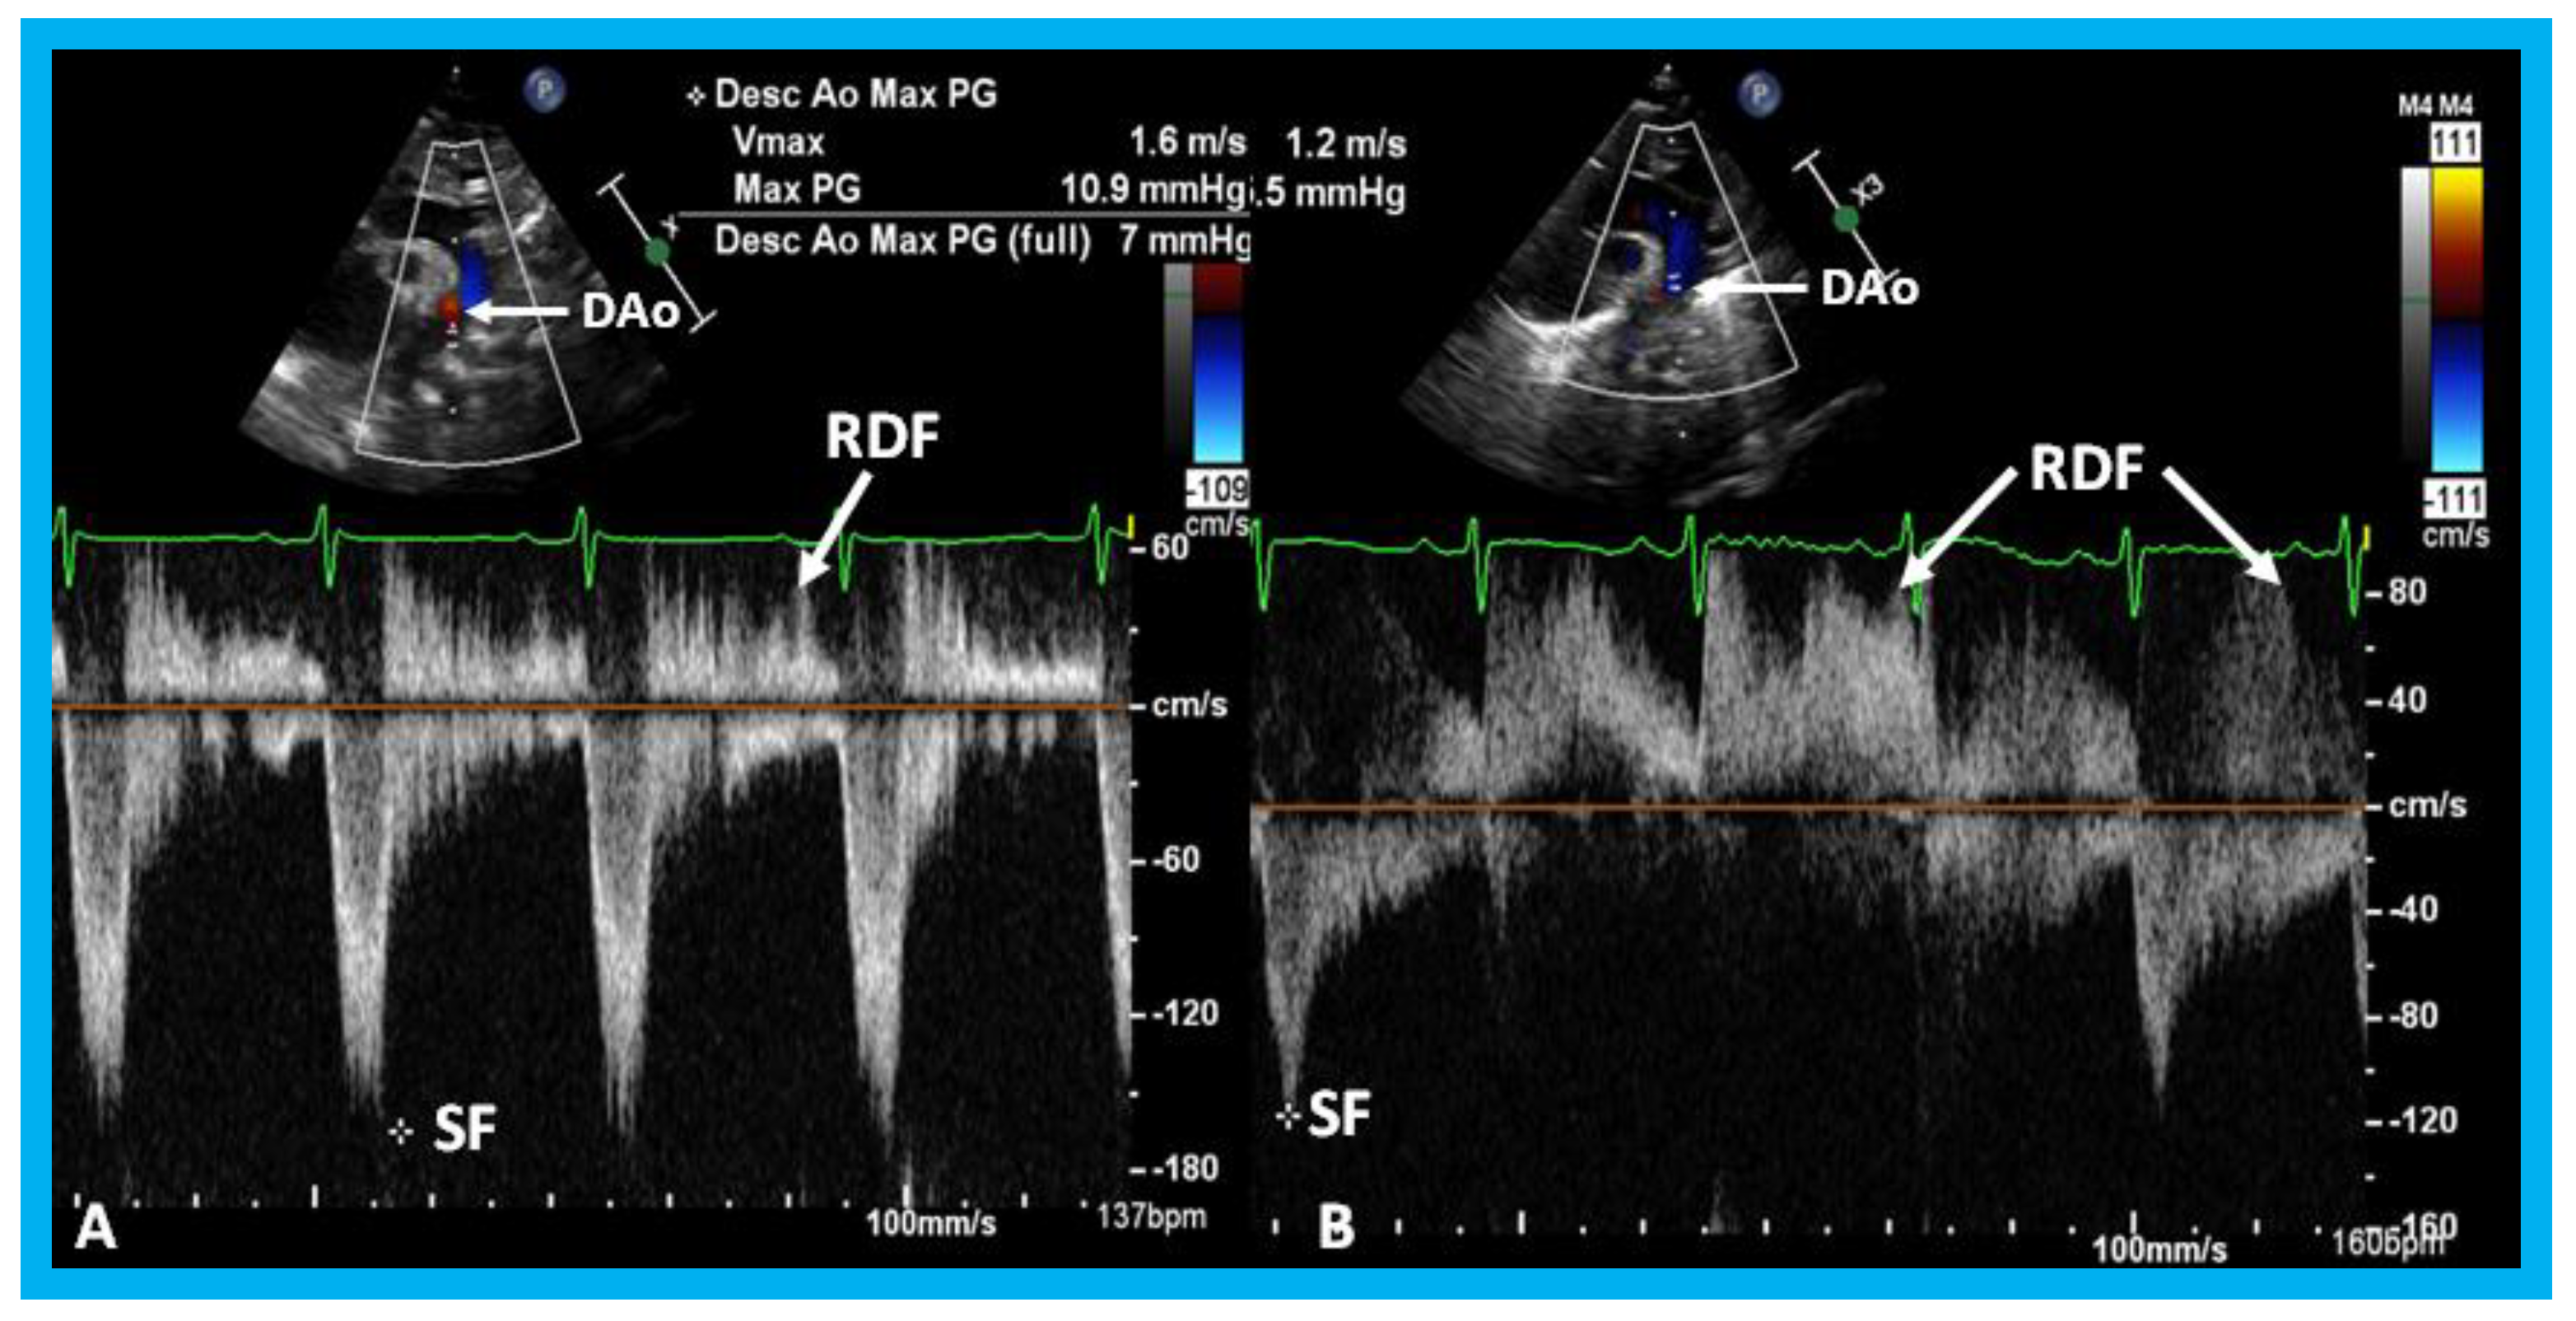

In small PDAs, the Minimal ductal diameter (MDD) is small and there is a high Doppler velocity across the PDA (Figure 32), while in large PDAs, the MDD is large and there is a low Doppler velocity across them (Figure 33). In moderately sized PDAs, these parameters are somewhere in between. The pulmonary artery (PA) pressures are usually normal in small PDAs, whereas the PA pressures are probably elevated in large PDAs. While the above statements are mostly accurate, the pressures in the PA also depend upon the magnitude of pulmonary parenchyma disease. Furthermore, in very low birth weight infants, the pressures in the PA may not be increased corresponding to the pulmonary parenchyma disease because of underdeveloped pulmonary vasculature in the premature.

Lastly, in small PDAs, normal diastolic anterograde flow is seen descending aorta (Figure 34), while in large PDAs, either no normal anterograde diastolic flow or retrograde diastolic flow (Figure 35) is seen in the descending aorta. Most of the medium-sized PDAs have normal diastolic anterograde flow in the descending aorta.